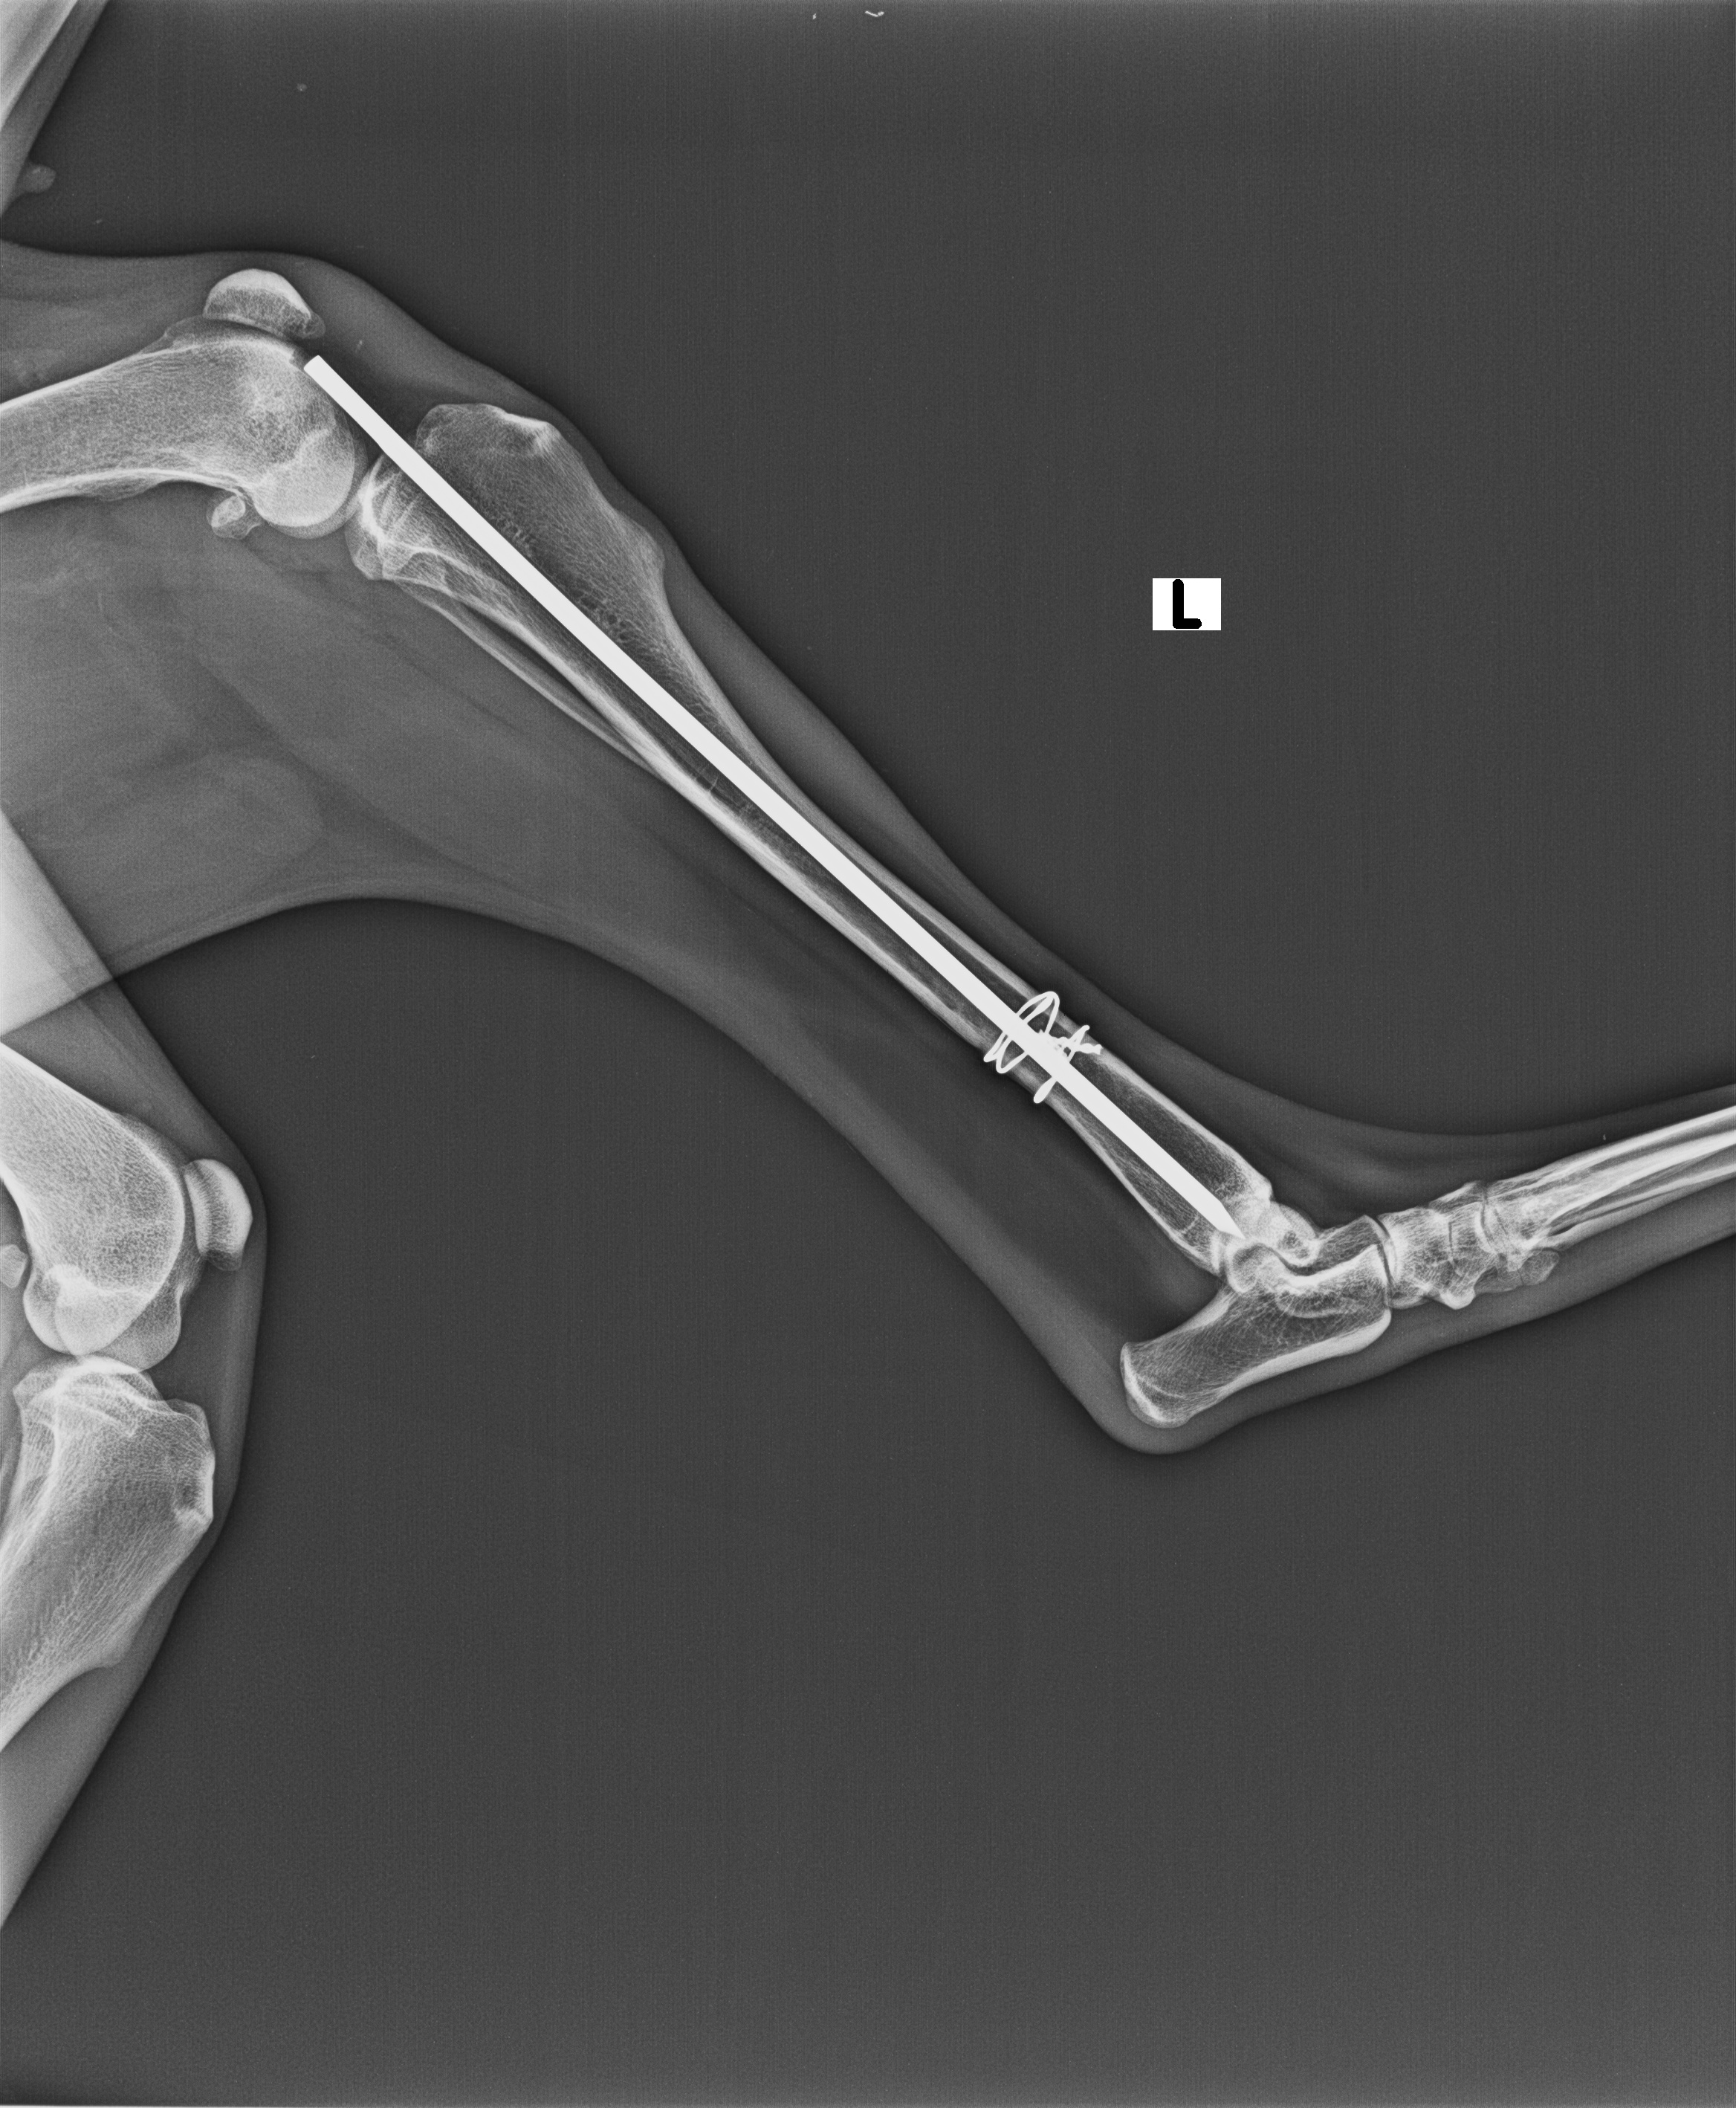

Prior Treatment/Surgery history : operation on same leg 2 years ago

Images / Radiology

X-RAY

Date | 12-06-2022 | Radiologist | Name of radiologist |

Description Lorem Ipsum is simply dummy text of the printing and typesetting industry. Lorem Ipsum has been the industry's stan |

Observation Lorem Ipsum is simply dummy text of the printing and typesetting industry. Lorem Ipsum has been the industry's stan |